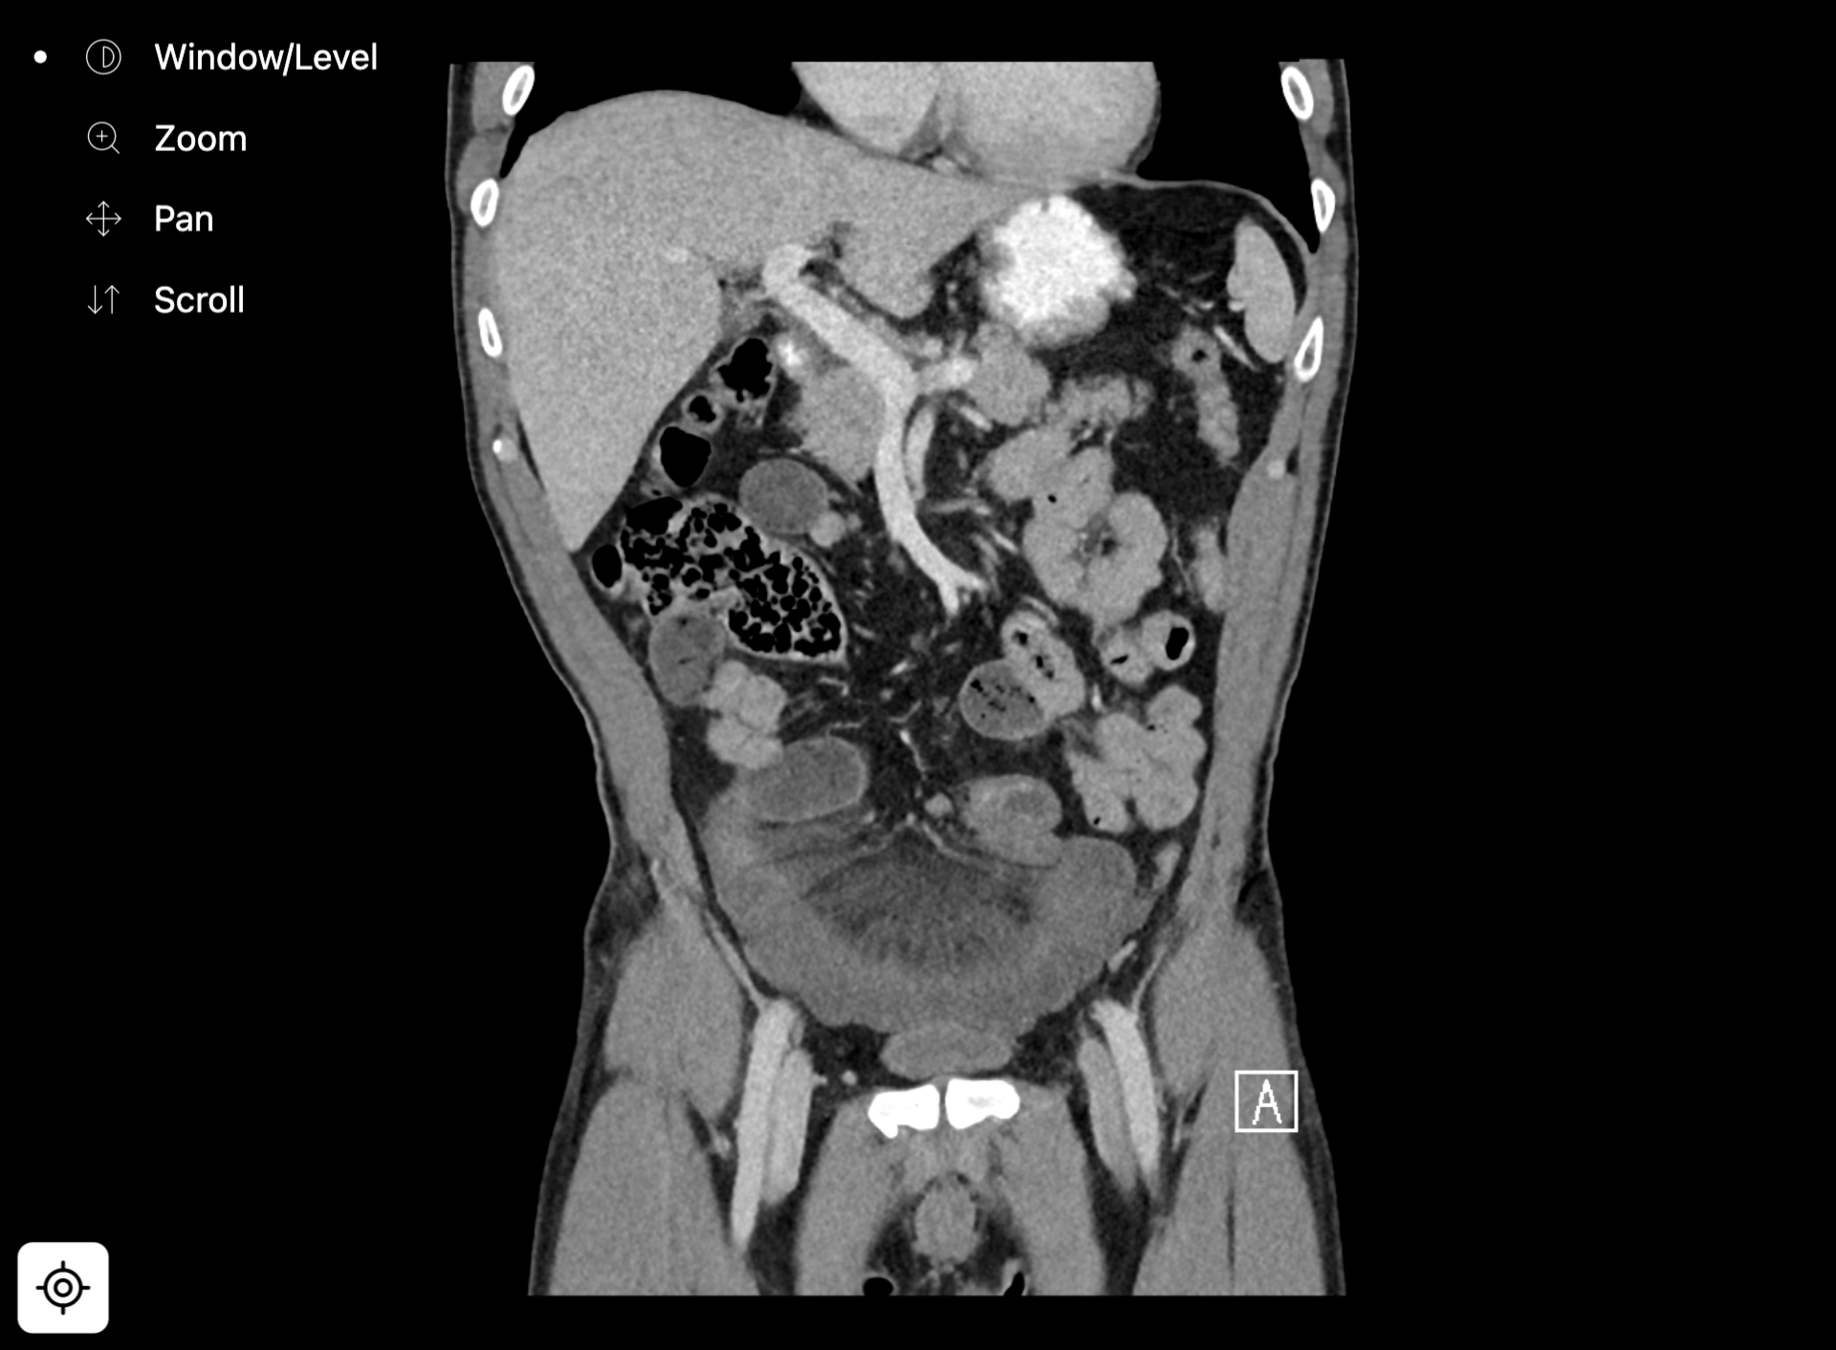

closed loop small bowel obstruction

notice how a single image can't show the entering and exiting transition points?